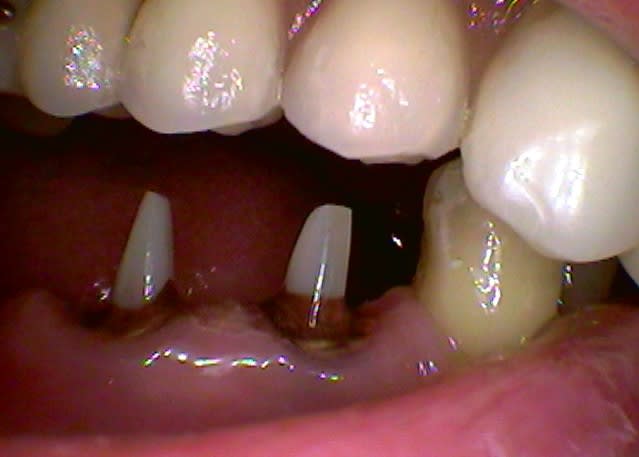

- pourquoi ne pas avoir attendu une quinzaine de jours, le temps que ta gencive cicatrise car elle a été bien "labourée" sur ce coup. C'est bien de vouloir tout gérer en une seule séance mais là on touche un point sur les limites du CEREC.

J'ai en effet taillé en pyramide car il ne me restait de valide qu'une partie du pan vestibulaire, et encore bien entamé par une profonde carie du collet heureusement sans contact pulpaire. J'aurai pu rajouter d'avantage de composite en OL, en général j'essaye de coller directement sur la dentine mais là il ne m'en restait que très peu...

J'aurai certainement obtenu un meilleur résultat en réduisant cette pyramide en hauteur forcément en l'aplatissant, mais je ne suis pas certain qu'un pilier plus large aurait changé grand chose, la MCXL gèrant bien les pans inclinés.

Avant d'avoir le Cerec, je reportais systématiquement mes empreintes à 1 semaine, maximum 10 jours, temps moyen de cicatrisation de la gencive lasérisée au CO². depuis, n'ayant plus besoin de placer de fil rétracteur, je réalise l'empreinte optique sans que la gencive soit forcée par le poudrage qui se dépose comme de la neige sur le sol et je peux t'assurer que la précision n'est pas altérée par l'aspect labouré de la gencive qui ne saigne pas par ailleurs.

Sur le cas ci-joint j'ai travaillé avec mon assistante le maquillage pour essayer de l'améliorer, mais c'est encore loin d'être parfait, il va falloir que je dorme avec le bouquin de Gérald Ubassy que j'ai reçu sous mon oreiller...